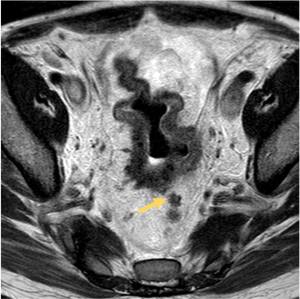

The imaging criteria for recurrence after complete response include:

- Increase in fibrotic scar depth angle >21°.

- Thickening of the fibrotic scar >10 mm (first sign of suspicion)

- New nodular areas with heterogeneous or intermediate T2 signal or diffusion restriction.